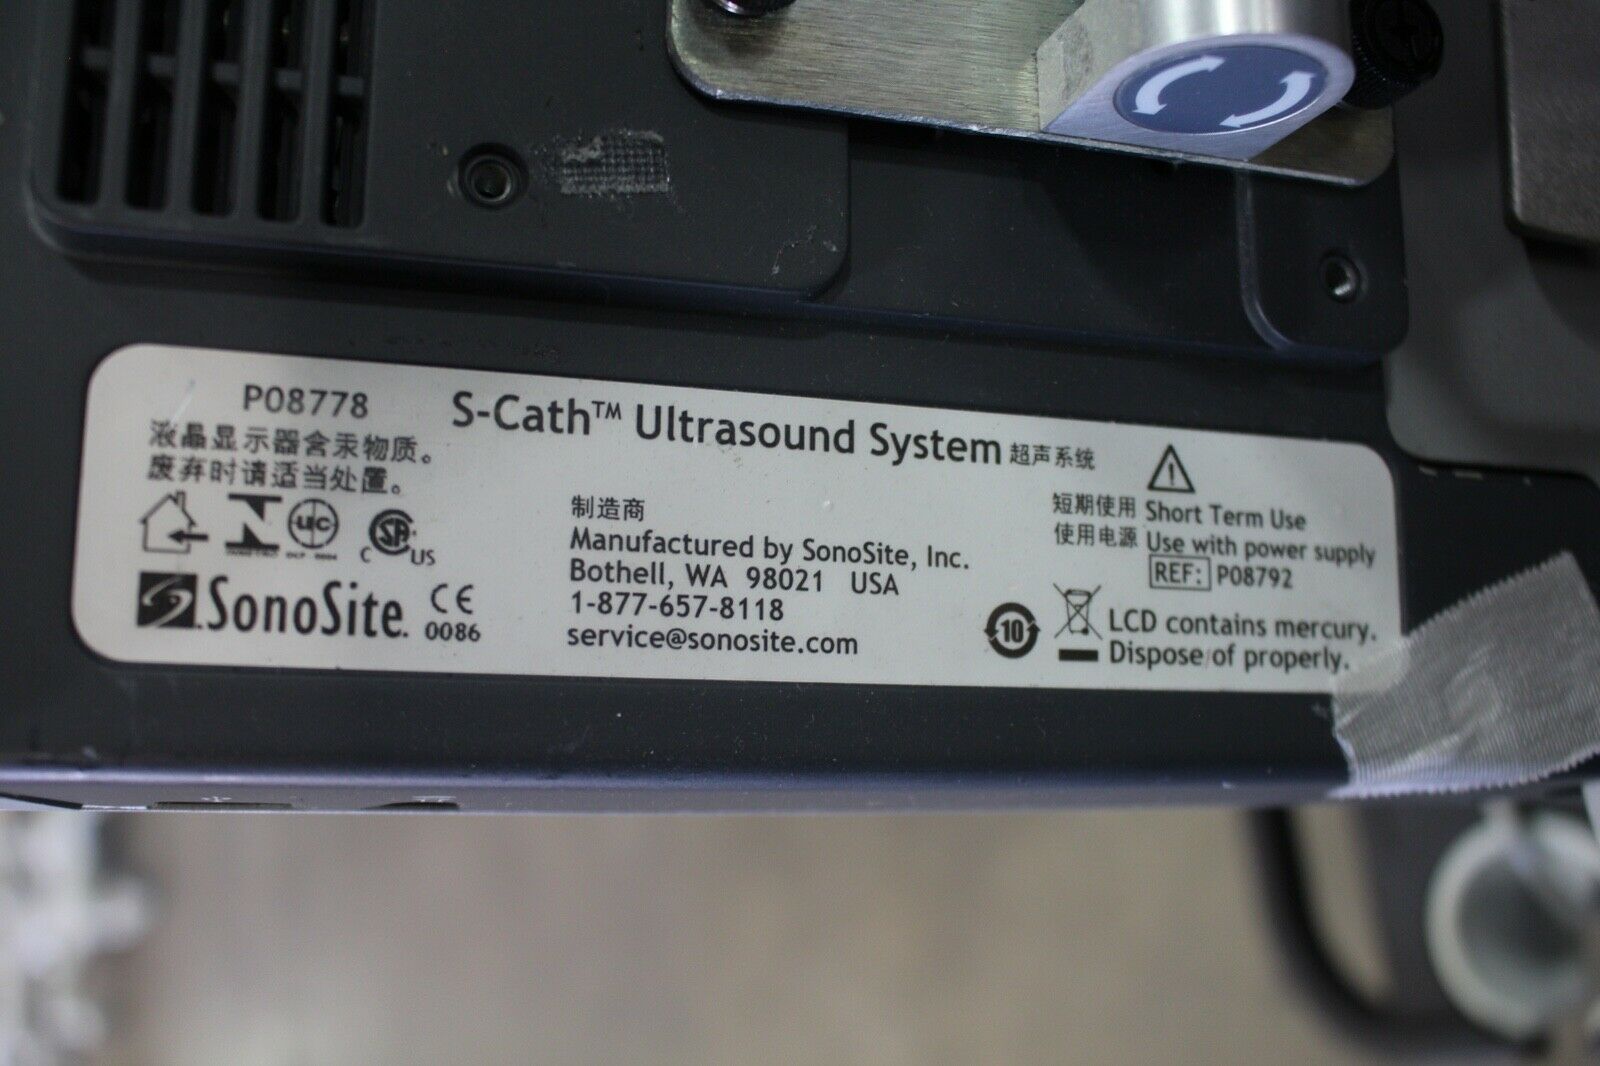

SonoSite S-Cath Ultrasound System WITH CART

Sale price$ 8,610.00